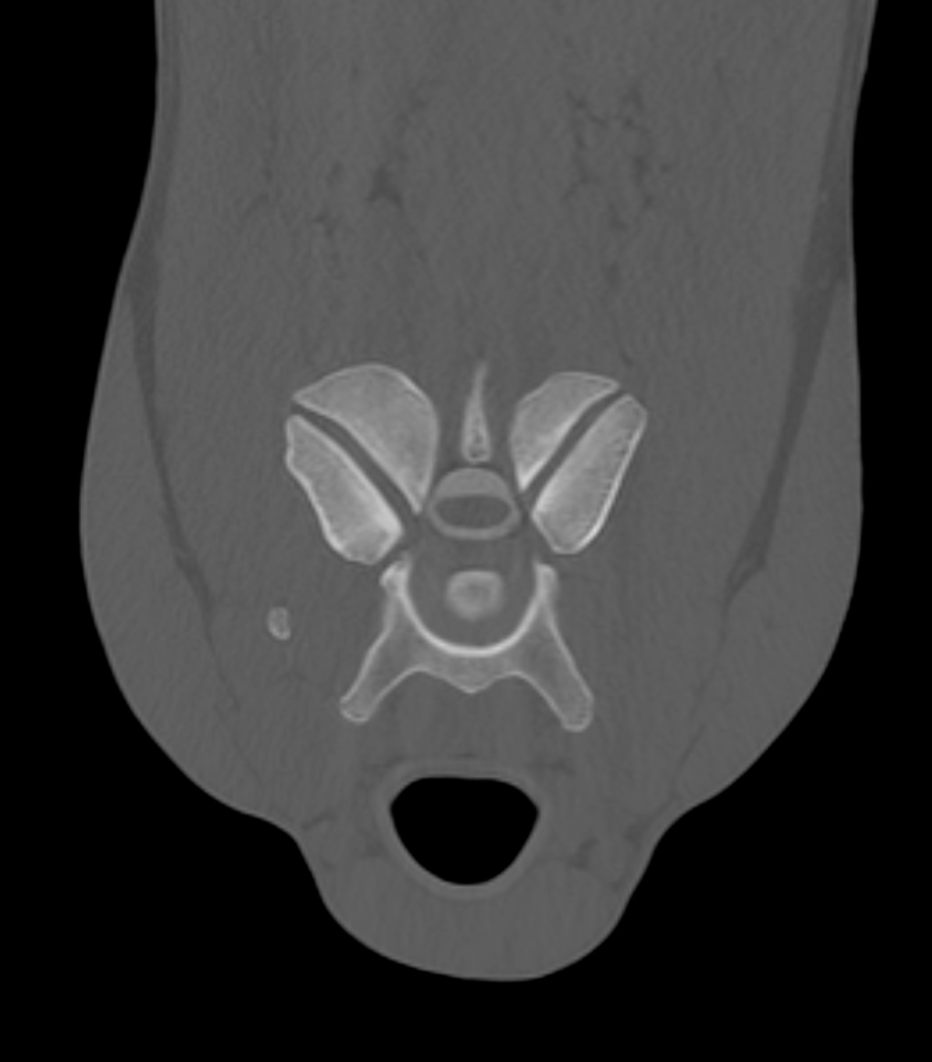

Professional reports with key images for all diagnostic imaging modalities, including radiographs, ultrasound, CT, MRI, nuclear scintigraphy.